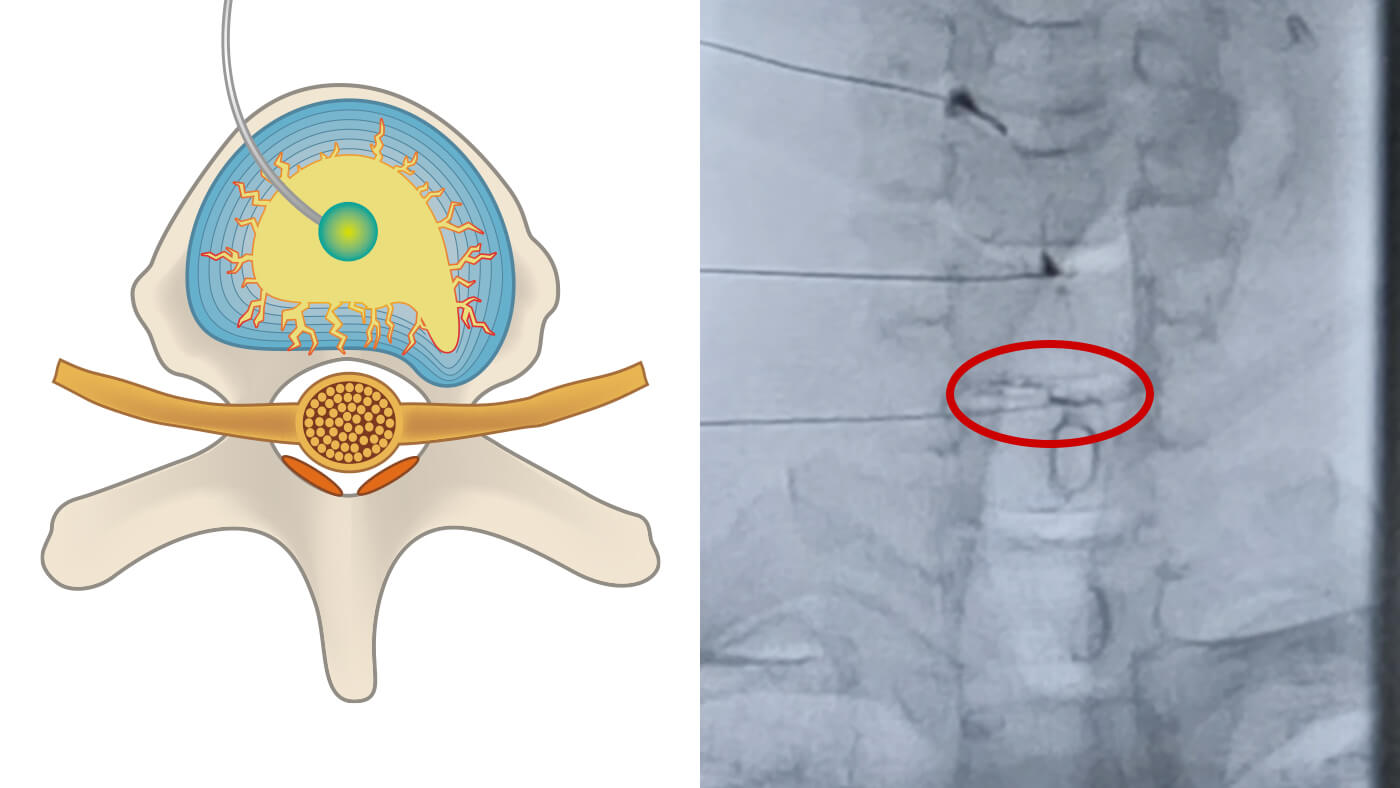

ディスクシール治療(The DISCSEEL® Procedure)は、椎間板の損傷に直接アプローチすることで、炎症に関与する症状改善を目的とした脊椎疾患に対する治療法です。2010年よりアメリカ合衆国テキサス州において、脊椎外科専門医ケビン・パウザ医師を中心としたチームにより研究・開発が行われています。

- ディスクシール治療では、損傷した椎間板そのものを治療対象とし、椎間板に直接アプローチします。

- 椎間板造影検査(アニュログラム)で椎間板の状態や漏れの部位を特定します。

- 椎間板の損傷に伴って生じる炎症の要因への対応を目的として行われます。